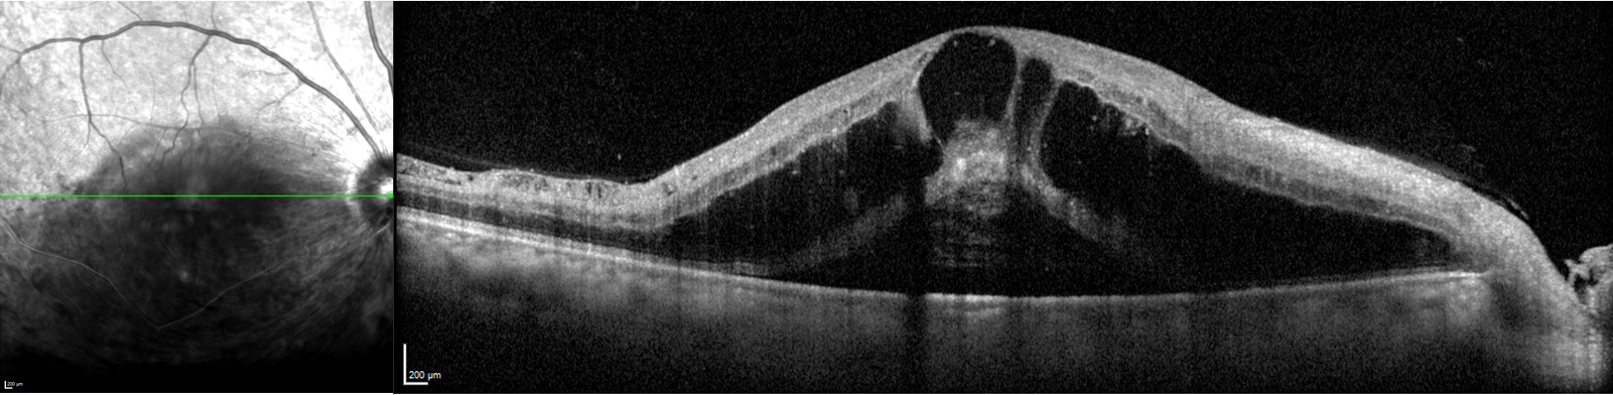

Des rétinophotos couleurs permettent de visualiser la veine concernée par l’occlusion, la présence d’hémorragies intra rétiniennes, de nodules cotonneux etc … L’OCT objective la présence d’un œdème maculaire et de mesurer son épaisseur. Enfin c’est l’angiographie à la fluorescéine qui nous renseigne sur l’état de la circulation du sang dans les vaisseaux rétiniens et la présence de complications ischémiques périphériques.

Coupe OCT maculaire montrant un œdème maculaire cystoïde post OBVR inférieure.

Le traitement dépend des complications retrouvées lors du bilan rétinien : œdème maculaire, ischémie périphérique ….

Un traitement par laser argon sera proposé en cas d’ischémie périphérique. Des injections intra vitréennes d’anti VEGF ou de corticoïdes sont proposées en cas d’œdème maculaire.

• Tomographie par Cohérence Optique (OCT) : Permet d'évaluer le degré de gonflement rétinien (œdème maculaire), la complication la plus fréquente et principale cause de la baisse de vision.